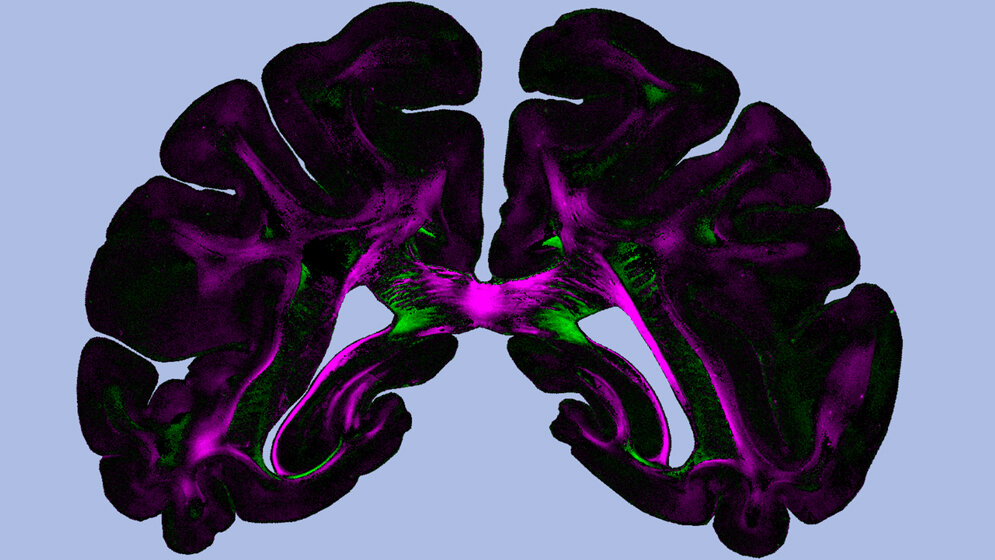

Beim „Diattenuation Imaging“ wird die Diattenuation-Messung mit einer 3D-PLI-Messung kombiniert. Damit lassen sich, wie die Forscher festgestellt haben, verschiedene Hirnregionen unterscheiden. Einige Regionen lassen am meisten Licht hindurch, wenn die Schwingungsrichtung des einfallenden Lichts parallel zur Faserrichtung verläuft. Andere sind maximal durchlässig, wenn die beiden Richtungen senkrecht aufeinander stehen. Wie sich das Gewebe verhält, hängt unter anderem von der Zeit ab, die nach der Eindeckung der Gehirnschnitte vergangen ist.

Daneben hängt der Effekt aber auch noch mit anderen Gewebeeigenschaften zusammen, etwa mit der Dicke der Nervenfasern und der umhüllenden Myelinscheide, wie die Forscher mithilfe von Simulationen am ehemaligen Jülicher Supercomputer JUQUEEN zeigen konnten. Auf diese Weise stellt „Diattenuation Imaging“ eine wichtige Ergänzung zu 3D-PLI dar und ermöglicht eine genauere Untersuchung von Hirngewebe. So könnte das Verfahren künftig zur Erforschung neurodegenerativer Erkrankungen wie Multiple Sklerose und Multisystematrophie (MSA) eingesetzt werden, die mit einer krankhaften Veränderung der Myelinscheide einhergehen. Darüber hinaus hilft die Technik, bei der ungeheuer komplexen Rekonstruktion des Gehirns zusammenhängende Regionen und Gewebetypen zu erkennen und pathologische Veränderungen sichtbar zu machen. (idw, red)